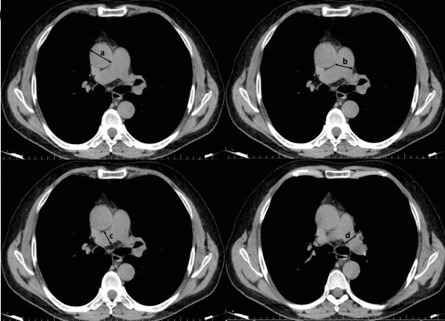

Materials and methods: In this study, we retrospectively examined the data of patients who were hospitalized and treated in our hospital between September 1, 2020, and November 30, 2020, and whose COVID-19 diagnosis was confirmed by reverse transcriptase polymerase chain reaction (RT-PCR). The diameters of the ascending aorta, main pulmonary artery, and right and left pulmonary arteries were measured from the chest computed tomography (CT) scans taken at the time of admission. The aim of the study was to investigate the impact of vascular diameters on the course of the disease.

Result: Of 1.705 patients, 840 were eligible for the study. We concluded that 36 of the patients (4.3%) died, and among the non-survivors patients, 12 (33.3%) were females, and 24 (66.7%) were males. Hospitalization duration was 7.1 ± 3.1 vs. 6.1 ± 2 days (p= 0.004) in surviving and non-surviving patients respectively. On the other hand, we found the mean diameters of the right pulmonary artery in the chest CT of patients to be 2.17 ± 0.35 vs. 2.44 ± 0.29 cm in survivors and non-survivors, respectively (p< 0.001). In addition, we found the mean diameters of the left pulmonary artery 2.12 ± 0.32 vs. 2.34 ± 0.28 cm in survivors and non-survivors, respectively (p< 0.001). Mean diameters of the ascending aorta were 3.53 ± 0.46 vs. 3.72 ± 0.34 cm in survivors and non-survivors, respectively (p= 0.017).

Conclusions: The study underscores the potential prognostic value of vascular diameters, especially in the ascending aorta and main pulmonary artery, as indicators of mortality risk in COVID-19 patients. The association between vascular dilation and severity of COVID-19, coupled with elevated D-dimer levels, suggests a link between thrombosis and vascular involvement.